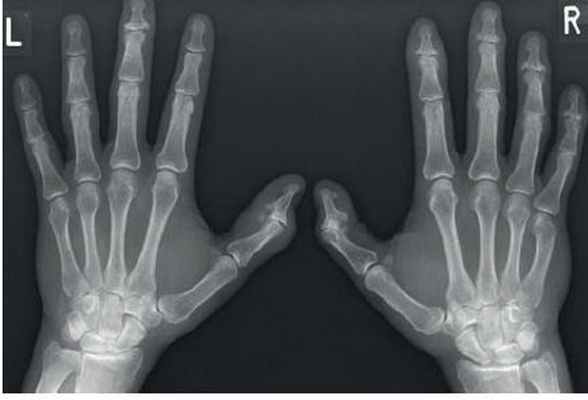

Дифференциальная диагностика заболеваний кисти

Рентгенография – отек мягких тканей вокруг суставов, остеопороз, сужение суставных щелей, краевые эрозии, субхондральные кисты и подвывихи, деформации кистей; вовлечение подтаранного сустава, эрозия заднего бугорка пяточной кости; эрозия дистальной части ключицы, краевые эрозии головки плечевой кости, субакромиальный бурсит; остеоартрит тазобедренных суставов с сужением суставных щелей; синовит коленного сустава, препателлярный бурсит; атланто-аксиальные подвывихи, эрозия зуба и остистых отростков.

Ревматоидный артрит. Эрозии головок метакарпальных костей. Сужение средних суставов пальцев.

Рентгенография: эрозивный остеоартрит в острой фазе с поражением дистальных и проксимальных межфаланговых суставов – субхондральные и центральные эрозии, но нет краевых эрозий; остеоартроз в хронической фазе (субхондральный склероз, остеофиты) и анкилоз

Остеартрит с типичным поражением первого карпо-метакарпального сустава. Сужение суставной щели. Остеофиты, субхондральный склероз.

3. Спондилоартропатии (серонегативные спондилоартритиды): псориатический артрит и синдром Рейтера (реактивный артрит), системная красная волчанка

Рентгенография: при синдроме Рейтера – поражение дистальных суставов по типу несимметричного олигоартрита, энтезит; при псориазе – краевые костные эрозии, периостит и поражение большого пальца стопы (“слоновая кость”) вследствие избыточного костеобразования; при системной красной волчанке – неэрозивные деформирующий артриты пальцев кистей и стоп с подвывихами

Псриатический артрит. Поражение дистальных фаланг с эрозиями и костной формацией ( палец).